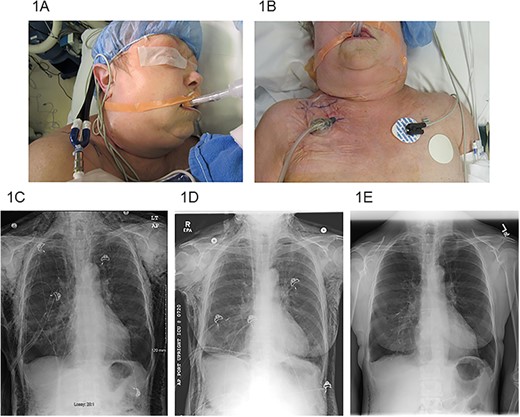

(A) SE extending to the periorbital region, (B) right infraclavicular incision location with VAC dressing, (C) pre-operative chest X-ray, (D) chest X-ray post-operative day #3 after VAC placement and (E) chest X-ray post-operative day #22 after VAC placement.

Three of the patients were male and two were female. The median age was 68 years (range 61–70). All patients had an extensive smoking history. All patients were treated with VATS resections: one wedge resection, one lobectomy, two combined lobectomy and wedge resections for NSLC, and one thymectomy with extensive adhesiolysis for a thymoma. Chest tubes were routinely placed on −20 cm H2O suction post-operatively. Initial efforts at management of SE included both increase in chest tube suction (range 25–40 cm H2O) and slight withdrawal of the chest tube (range 2–5 cm). The VAC dressing was placed a median of 6 days after the initial operation (range 3–19 days). Median overall length of stay was 16 days (range 7–23). Median length of VAC treatment was 10 days (range 4–15). All patients had immediate improvement in symptoms and quick resolution of SE by the VAC dressing therapy (Fig. 1C–E). All patients were successfully discharged home. One patient was discharged without a chest tube or VAC therapy, one patient required a chest tube with Heimlich valve, two patients required only VAC therapy, and one patient required both VAC therapy and chest tube with Heimlich valve at discharge. No complications of incision or VAC dressing placement were observed.